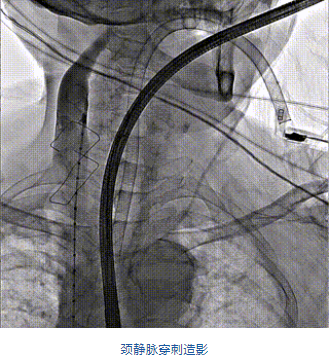

團隊前期經(jīng)過多次討論,制定了周密的手術(shù)策略和預(yù)案。由于患者已是近九旬的超高齡老人,傳統(tǒng)外科開胸手術(shù)風(fēng)險極高,純介入經(jīng)血管三尖瓣替換能夠明顯減少創(chuàng)傷。術(shù)中陳茂及馮沅教授結(jié)合體表定位在造影指示下精準穿刺右側(cè)頸靜脈并預(yù)置兩把血管縫合器。成功建立經(jīng)皮血管入路后在食道超聲和DSA的引導(dǎo)下順利完成人工瓣膜植入,術(shù)后超聲和造影顯示人工三尖瓣同軸性良好,瓣架固定牢靠,無反流和瓣周漏,平均跨瓣壓差降為1mmHg。術(shù)畢收緊預(yù)置的血管縫合器縫線完成止血,縫合效果滿意,在手術(shù)室即刻拔除氣管插管。